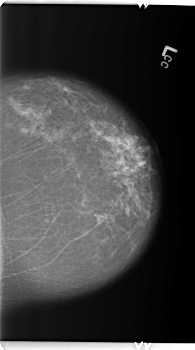

B_3362_1.LEFT_CC

LEFT_CC LINES 5936 PIXELS_PER_LINE 3304 BITS_PER_PIXEL 12 RESOLUTION 50 NON_OVERLAY